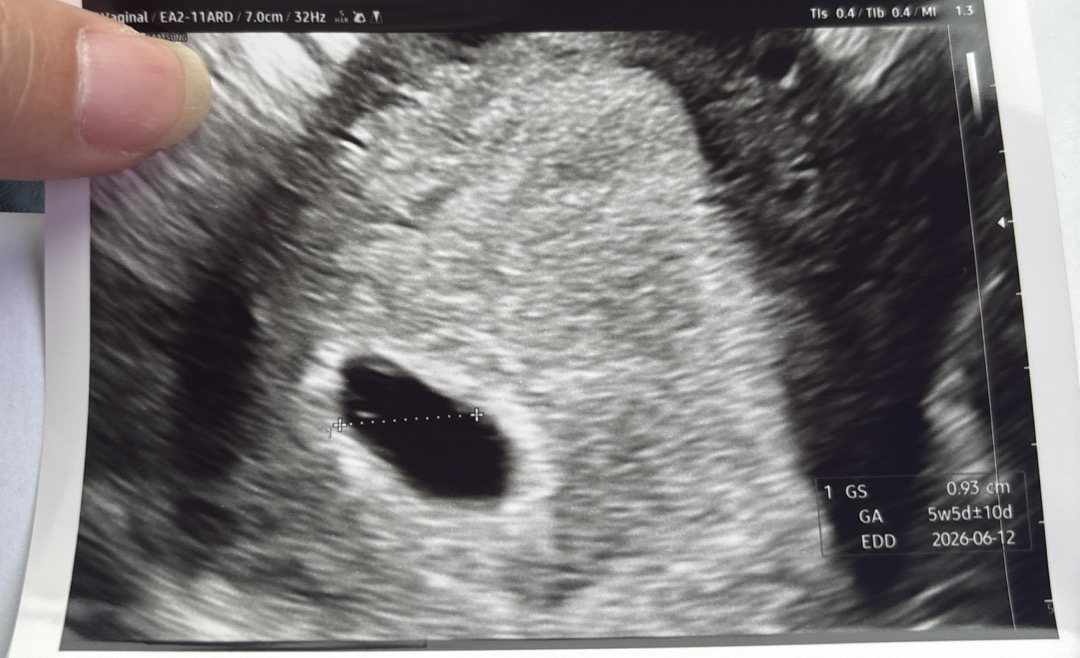

난황이 참깨만하게 보이신다고 하는데 저는 안보여요ㅠ 보이신가여..?

아기집 왼쪽에 점선 바로 위에있는 참깨말하시는거 아닐까요오~?

저렇게작은게 정상일까요??